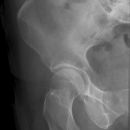

Hüfte nach Lauenstein II (15°)

Beurteilung des Schenkelhalses

KONTRAINDIKATION: frische Fraktur und Luxation

Gute Beurteilung des Hüftkopfes, der Pfanne und des Schenkelhalses. Der Trochanter major überdeckt bei teilweise den Schenkelhals.